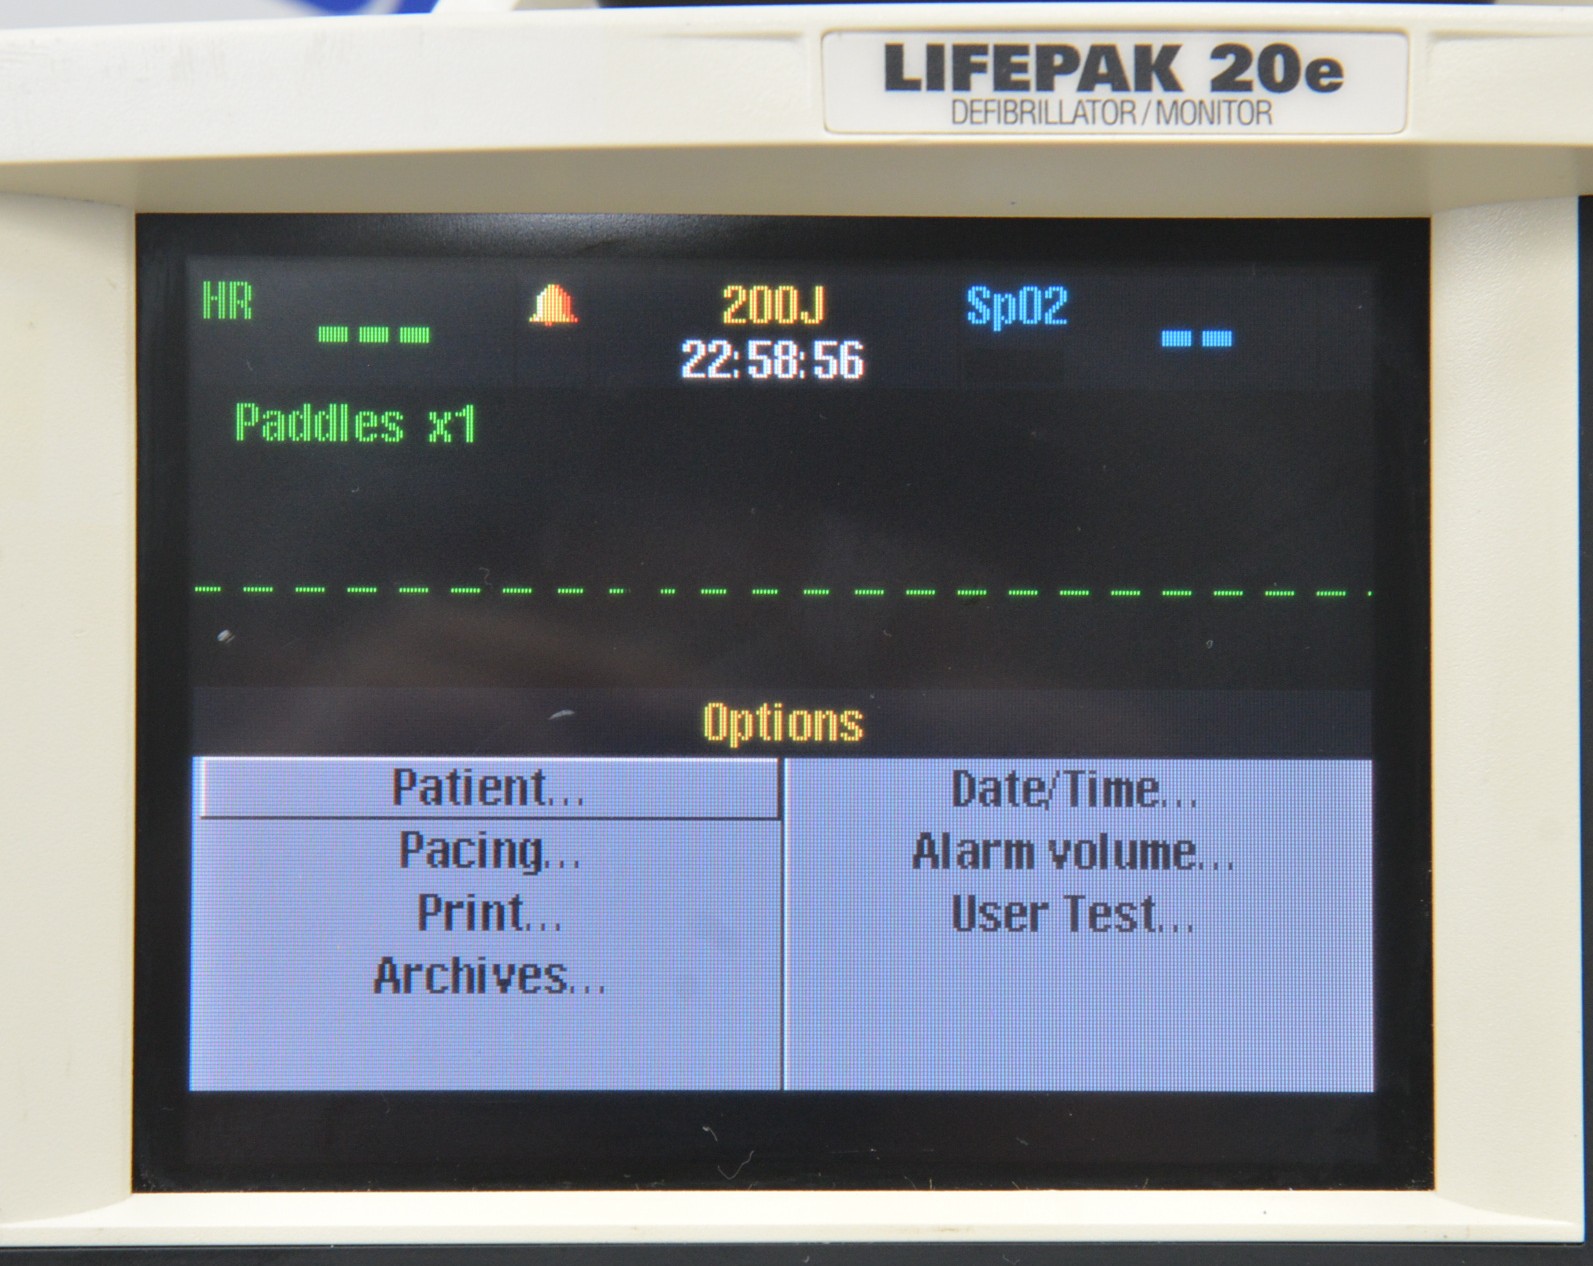

This Medtronic Lifepak 20e Defibrillator Monitor 2010 W/ Paddles is in good working condition. The unit powers on properly and responds to selections. All connection points are clean and in good condition. There are some scuff marks from previous use (see photos). This unit comes with a 30 day satisfaction guarantee. Includes everything in the pictures and nothing else.